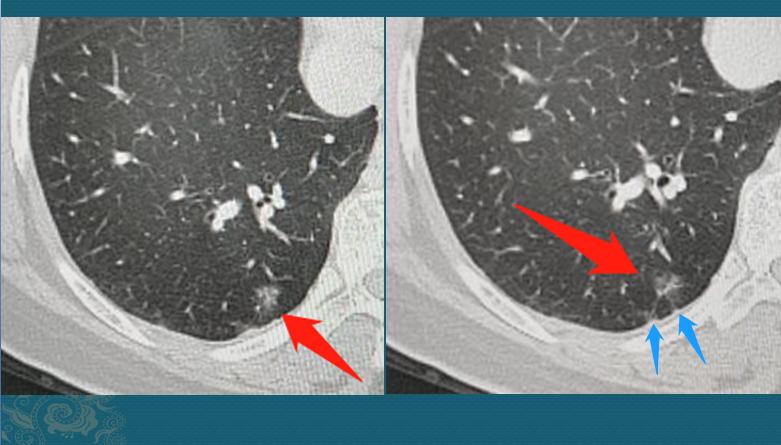

因为疫情缘故,她在8个月的时候回来复查了CT,左边的没有变化,右边的长大了:

8个月的时间,从一个不足3mm的微结节,长成9mm的磨玻璃结节,速度非常快!以至于我们不敢确定就是肺癌。

我们把图像放大再看看细节,这个磨玻璃结节边界不清晰,内部有血管穿行,并略增粗,边缘有两处细线状胸膜牵拉,病人也没有咳嗽、发热症状,炎性指标都正常,这些辅助资料不太支持炎症: